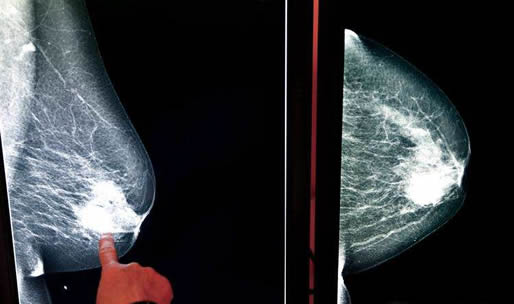

和其它恶性肿瘤相似,乳腺癌的常见疗法主要有手术、化疗、放疗、内分泌治疗、免疫治疗等等。

因为乳腺器官的重要性相对较低,不会危及生命,所以当前切除手术是处理乳腺癌最为主要的办法,比较适合早期和癌细胞未转移的患者。